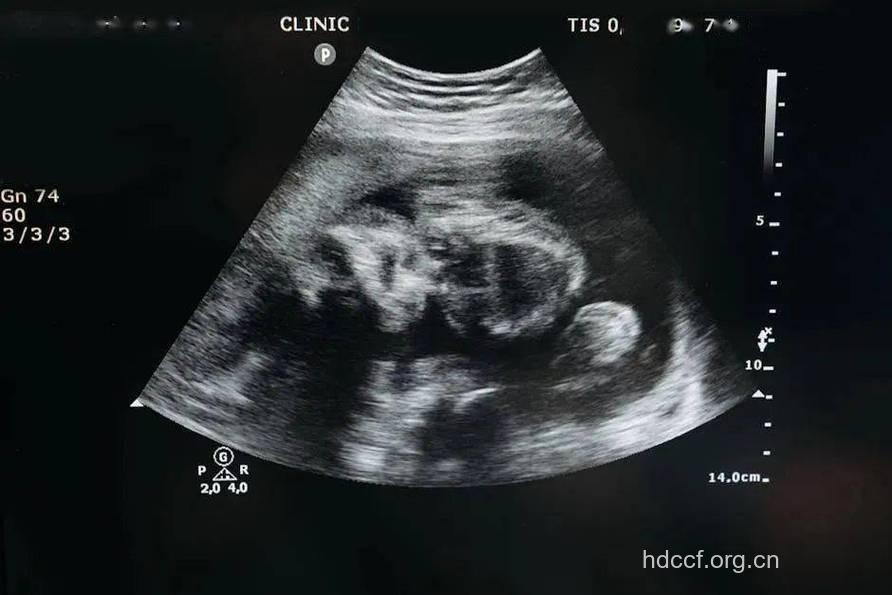

很多怀孕的妈妈们都渴望时时刻刻了解宝宝的情况,是否健康,不定期就会到医院进行产前检查,照B超是常见的检查手段,但是经常去照B超对孩子好吗?会不会对胎儿有不良的影响呢?